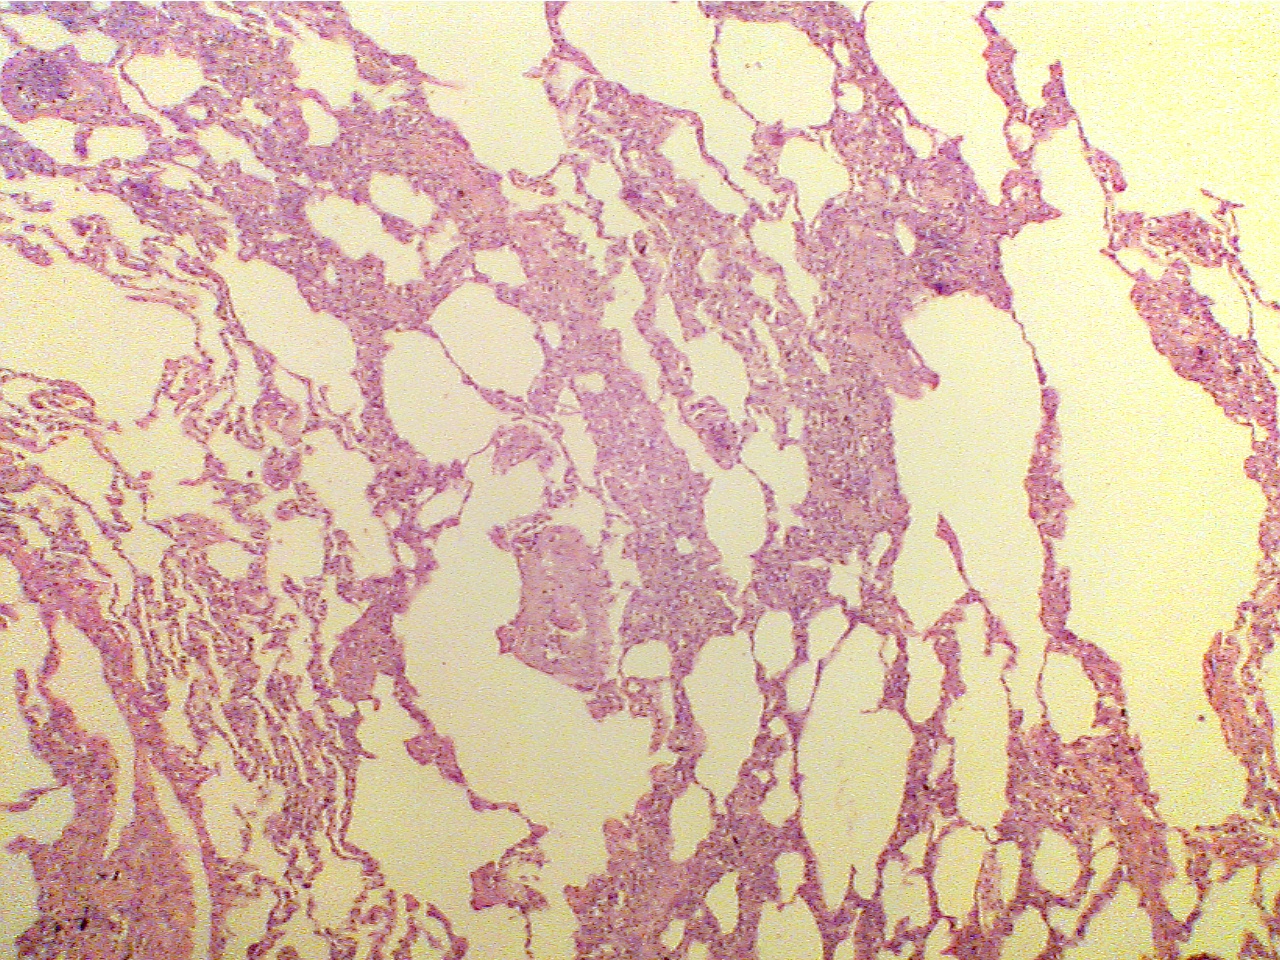

Note that the cancerous neoplasm is invading throughout the lung and replacing normal lung tissue. Note that in many areas the alveolar walls are thickened and many air spaces are filled with cancer cells.

Normal lung (100X2.0)                                                                       Lung with cancer (100X2.0)

Contains mostly thin membranes, open air-filled                   Contains thickened membranes, cancer cells fill many

spaces, and many small vessels (bright red)                          air spaces and vessels